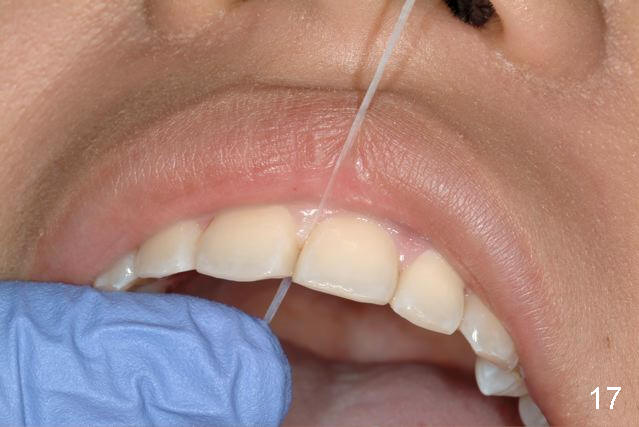

Amy can floss with her retainer...